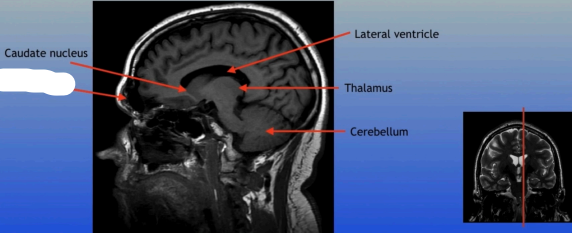

Caudate Nucleus

A C-shaped structure within the brain's basal ganglia, involved in various functions including motor control and learning.

Lateral Ventricle

A fluid-filled cavity located within each hemisphere of the brain, part of the ventricular system, that helps cushion the brain and circulate cerebrospinal fluid.

Thalamus

A large mass of gray matter located in the diencephalon, acting as a relay station for sensory information and playing a key role in regulating consciousness and sleep.

Cerebellum

A large structure located at the back of the brain responsible for coordination, balance, and fine motor control.